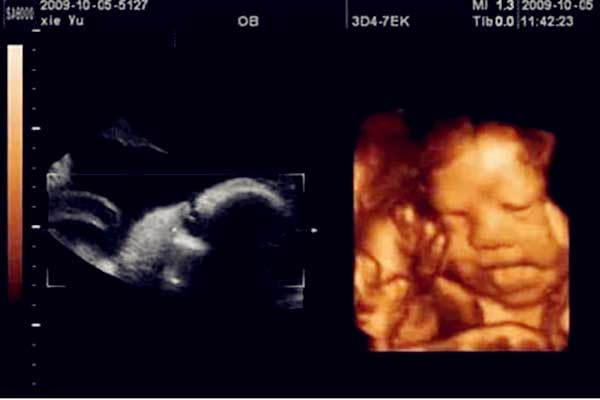

怀孕5个月男女肚型图,怀孕5个月胎儿真实彩超图。

怀孕5个月男女肚型图,怀孕5个月胎儿真实彩超图快来看看吧!当进入怀孕的第五个月时,妈妈们会发现许多有趣的事情,比如胎儿宝宝此时能够与你互动游戏了,比如胎儿喜欢听到..